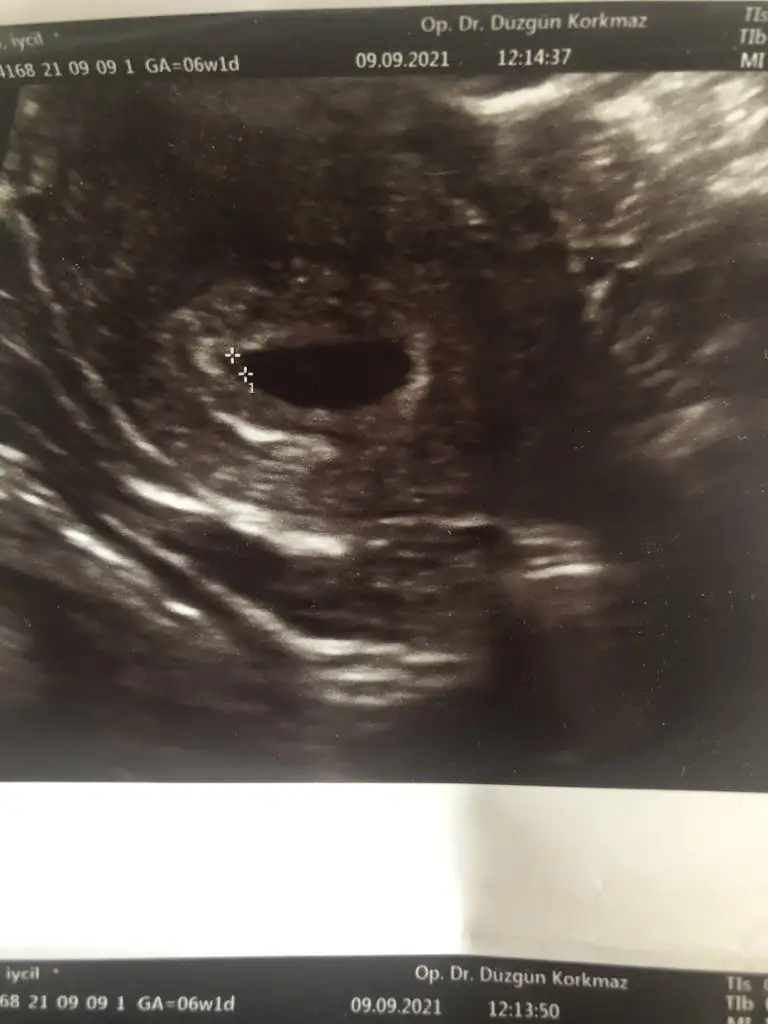

Benimki 6+1 bu şekilde canımKızlar 6+4 ve yakınlarında gidip ultrason görüntüsü aldıysanız bir paylaşabilir misiniz rica etsem

Teşekkür ederim Peki kalp atışı duymuş muydun bu ultrasonda?Benimki 6+1 bu şekilde canım

Evet canım çok yüksek olmasada duymuştum. Ama bizim bebiş günüyle uyumlu gidiyor senin için perşembeden beri rahat değil istersen farklı bir doktora gidersen dinletir belki ya da gösterir ve için rahatlayabilir. İnsan ister istemez olumsuzu düşünüyor ama senin olumsuz düşüneceğin bir durum yok doktorunda daha erken demiş olumsuz birşey söylememiş güzel düşünelim güzel olsunTeşekkür ederim Peki kalp atışı duymuş muydun bu ultrasonda?